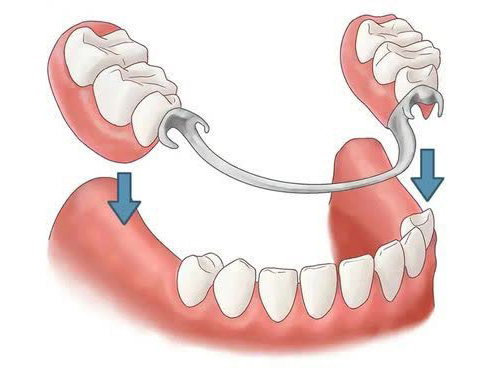

پروتزهای دندانی، چه ثابت و چه متحرک، نقش بسیار مهمی در بازگرداندن عملکرد طبیعی دهان، زیبایی لبخند و اعتمادبهنفس بیماران دارند. با این حال، بسیاری از بیماران تصور میکنند پس از گذشت چند ماه از نصب پروتز، دیگر نیازی به مراقبتهای ویژه نیست؛ در حالی که مراقبت از پروتز پس از ۶ ماه یکی از حساسترین و مهمترین مراحل در حفظ سلامت دهان و افزایش طول عمر پروتز به شمار میرود. در این بازه زمانی، پروتز با محیط دهان سازگار شده، اما همزمان ممکن است تغییرات ظریفی در لثه، استخوان فک یا حتی ساختار خود پروتز ایجاد شود که بدون مراقبت صحیح، به مشکلات جدیتری منجر خواهد شد.

پس از گذشت حدود شش ماه از نصب پروتز دندانی، دهان وارد مرحلهای میشود که تطابق اولیه کامل شده است. در این زمان، لثهها شکل نهایی خود را پیدا میکنند و فشارهای ناشی از جویدن بهطور مداوم به پروتز منتقل میشود. اگر مراقبت از پروتز در این مرحله بهدرستی انجام نشود، احتمال بروز مشکلاتی مانند التهاب لثه، تجمع پلاک میکروبی زیر پروتز، بوی بد دهان و حتی تحلیل استخوان فک افزایش مییابد.

یکی از نکات مهمی که بسیاری از بیماران از آن غافل میشوند، تغییرات طبیعی لثه و استخوان فک پس از نصب پروتز است. حتی در بهترین شرایط، بافتهای دهان ممکن است بهمرور زمان دچار تغییر شکل شوند. این تغییرات میتوانند باعث ایجاد فاصله بین پروتز و لثه یا احساس لق شدن پروتز شوند.

در چارچوب مراقبت از پروتز، بررسی دورهای لثهها اهمیت بالایی دارد. علائمی مانند قرمزی، تورم، خونریزی هنگام مسواک زدن یا درد مزمن نباید نادیده گرفته شوند. این نشانهها میتوانند هشداری برای التهاب لثه یا فشار نامناسب پروتز باشند. مراجعه منظم به دندانپزشک امکان تنظیم یا اصلاح پروتز را فراهم میکند و از بروز آسیبهای جدیتر جلوگیری خواهد کرد.